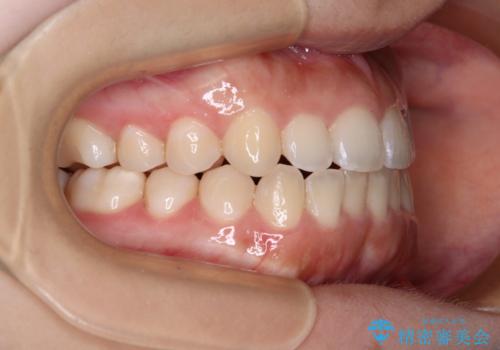

前歯のクロスバイトを改善 インビザライン・モデレートによる矯正治療

- 上下前歯のクロスバイトと叢生を気にして来院された患者様です。

インビザラインでの治療を希望されていて、デコボコの程度が中等度であり、安価なパッケージにて対応可能と判断されたため、インビザライン・モデレートを用いて矯正治療を行うこととしました。